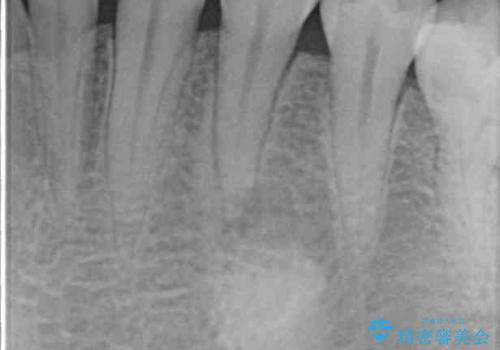

レントゲン写真などで診査を行ったところ、左下の第一小臼歯の神経組織が壊死し、根尖部周辺の骨に炎症が認められました。

根管治療後6ヶ月でレントゲン写真を撮影したところ、根尖部周辺の炎症が消退していることが認められました。